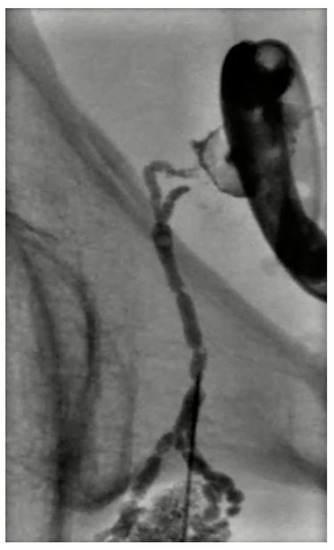

- Retromolar trigone: This is the space between the last molar and the mandibular condyle. It is a space without many vessels/nerves or vital structures; therefore, it represents a safe approach to treating pharyngeal and laryngeal lesions. Tongue positioning is mandatory, as it can flop backward against the ablation site resulting in frost injury: Forceps and a laryngoscope should be used to displace the tongue with gauze away from the ablation site to avoid this occurrence. In the case of tumors near the carotid artery, the patient can manifest severe hypotension and bradycardia during ablation. The presence of coils or metallic devices in a previously embolized carotid artery leads both to a loss of the cold-sink effect as well as a stimulation of the vagus nerve with thermal conduction down the carotid body (leading to the diving reflex). Cessation of cryoablation usually leads to spontaneous resolution (Figure 2).